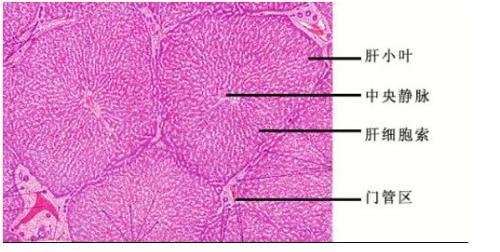

肝小叶

肝小叶汇管区小叶间静脉 小叶间动脉和小叶间胆管的区别

淋巴管的分支,可见小叶间静脉,小叶间动脉和小叶间胆管,该区域称为 肝

肝小叶的结构

肝小叶结构图